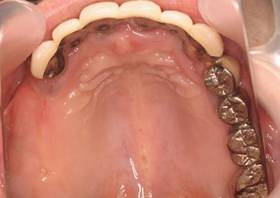

術後。上部構造はハイブリッドレジンです。しっかり嚙めるようになり喜んでいただきました。

上顎

下顎

上部構造装着後6年。ハイブリッドレジンを使用したため、少し艶がなくなってきました。上部構造の材料には金属、ハイブリッドレジン、セラミックなどがあります。セラミックはきれいですが欠けやすいため、最近はフルジルコニアを使っています。

上顎 少しすり減ってきました。

下顎。12か月に一度メインテナンスをしています。